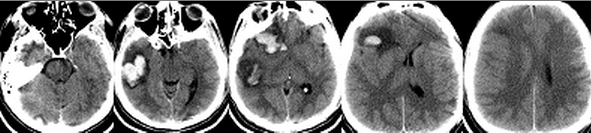

Пациент Д, 26 лет, был переведен в Институт из стационара первичной госпитализации на третьи сутки после травмы с диагнозом: Тяжелая открытая ЧМТ, ушиб головного мозга, вдавленный перелом костей черепа в теменной области по средней линии. Из анамнеза было известно, что пациент был избит. При поступлении в Институт уровень сознания оценивался как сомноленция. Очагового неврологического дефицита не выявлялось. При КТ-исследовании головного мозга определялись множественные геморрагические очаги ушибов III-IV вида в правой лобно-височной области с перифокальными зонами отека. Срединные структуры были смещены влево на 5 мм, желудочковая система сужена. Конвекситальные субарахноидальные пространства правого полушария сглажены. Определялся вдаленный оскольчатый перелом в правой теменно-парасагиттальной области, линейный перелом в левой теменно-височной области и расхождение сагиттального шва (Рисунок 3).

Пациент находился в нейрохирургическом отделении. Через несколько часов после госпитализации в Институт состояние пациента стало прогрессивно ухудшаться. Развилось угнетение сознания до сопора, появилась брадикардия и артериальная гипертензия. Экстренно была выполнена операция - устранение вдавленного перелома в правой теменно-парасагиттальной области. После операции больной переведен в отделение реанимации, где был начат мониторинг ВЧД. При пробуждении развивалась внутричерепная гипертензия, поэтому проводилась седация. Продолжалась ИВЛ. Показатели гемодинамики оставались в пределах нормы. Появилась лихорадка до 39-39°С резистентная к терапии нестероидными противовоспалительными препаратами, парацетамолом и наркотическими анальгетиками. В течение суток состояние оставалось стабильным. На 2 сутки после операции (5 сутки после травмы) развилась устойчивая ВЧГ (35-40 мм.рт.ст.), резистентная к углублению седации и терапии гиперосмолярными растворами (маннитол, гиперХАЕС). Было принято решение о проведении ИГ. Была установлена система CG, начата инфузия ледяного физиологического раствора в соответствии с протоколом. Однако спустя 4 часа у пациента сохранялась температура 37-37,8°С в мочевом пузыре. Выраженность ВЧГ существенно уменьшилась, однако, ВЧД оставалось на уровне 22-25 мм.рт.ст. Это стало основанием для комбинации методов достижения гипотермии. Пациент был уложен на охлаждающий матрац с установкой целевой температуры 32°С. Вместе с этим пациенту осуществлялась инфузия пропофола, фентанила и пипекурония. Не смотря на агрессивность проводимой терапии, гипотермии удалось добиться только через 18 часов после начала охлаждения. В течение последующих 3 суток на фоне проводимой ИГ отмечались редкие эпизоды ВЧГ, которые корригировались введением гиперосмолярных растворов. Это привело к развитию гипернатриемии. В связи с этим было принято решение о выполнении декомпрессивной краниотомии с пластикой твердой мозговой оболочки на 6 сутки после первой операции (9 сутки после травмы). После краниотомии ИГ проводилась еще в течение 2 суток. ВЧГ на этапе согревания не возникало. Показатели витальных функций были в пределах нормы. Седация прекращена на следующие сутки после достижения нормотермии. Сознание восстановилось на 14 сутки после травмы, а адекватное самостоятельное дыхание – на 20 сутки. Затем пациент был переведен в нейрохирургическое отделение. На 52 сутки после травмы пациент был выписан из Института в удовлетворительном состоянии без очагового неврологического дефицита.